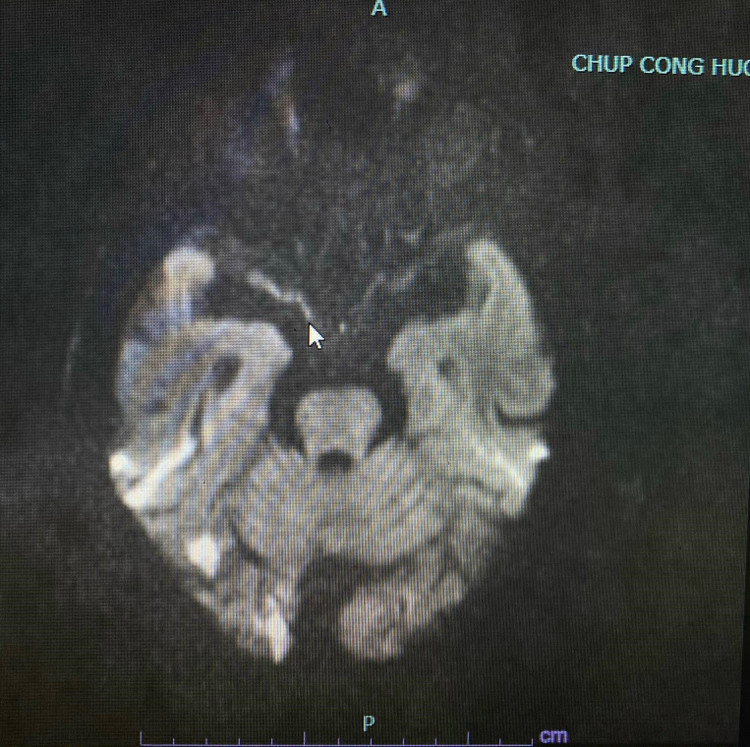

Bệnh nhân đã được khám và tư vấn chụp cộng hưởng từ sọ não: có hình ảnh tổn thương tiểu não, thân não do tắc thân nền nhưng quá giờ can thiệp. Bệnh nhân và gia đình đã bỏ qua thời gian vàng để cứu sống bệnh nhân.

| Hình ảnh tổn thương trên phim chụp |